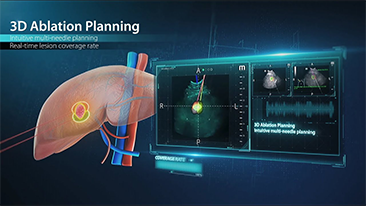

Wie deutlich k?nnen Sie eine Leber erkennen?

Bei fokalen Leberl?sionen wie H?mangiomen oder Leberkrebs spielt die Ultraschallkontrastdarstellung eine zentrale Rolle. Mit der weitreichenden nichtlinearen UWN+Kontrast-Bildgebungstechnologie k?nnen eine bessere Penetration, ein h?heres Kontrast-Gewebe-Verh?ltnis, eine geringere MI und eine l?ngere Beobachtung der Durchblutungsdauer erreicht werden.